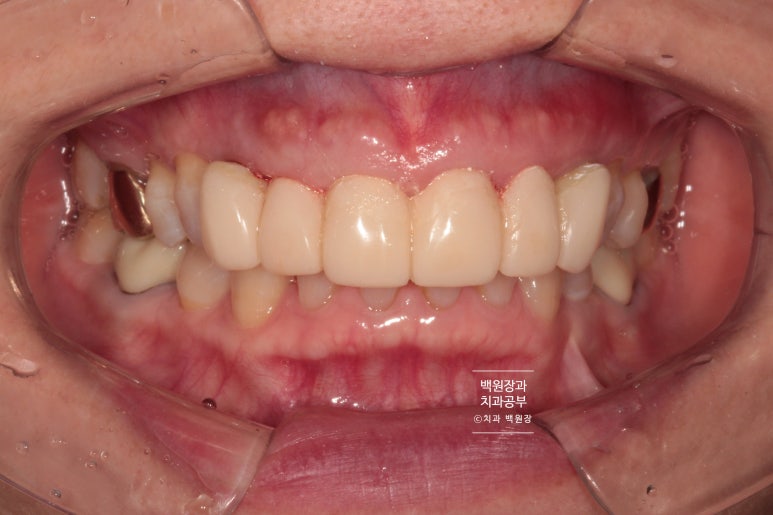

이렇게 봤을 때는 큰 문제가 없어보이는 앞니를 가진 환자분이었습니다.

아래 앞니에 치석이 조금 보이지만... 그리고 위 앞니에 크라운 치료를 받으시고 오래되서 뿌리 노출이 조금 있긴 하지만, 기능적으로 큰 문제는 없어보이죠?

상당히 자연스러운 색상과 외형을 가진 보철물로 제작이 잘 되었네요!

여성분이라 잇몸의 두께가 얇아 임플란트의 경우 내부의 맞춤형 지대주 (custom abutment)가 약~간 비춰보이는 경향은 있으나, 사실 본인이 아니고서야 이게 자연치인지 크라운인지 임플란트인지 분간조차 어려울 거에요.

측면에서 보아도 자연스러운 외형을 관찰할 수 있고, 이차 충치가 생기거나 잇몸질환이 생기는 것을 방치하기 위하여 4개의 치아와 2개의 임플란트 모두 크라운을 따로따로 제작하였습니다.

씹는면에서 바라보았을 때도 자연스러운 모양과 색상을 관찰할 수 있습니다.